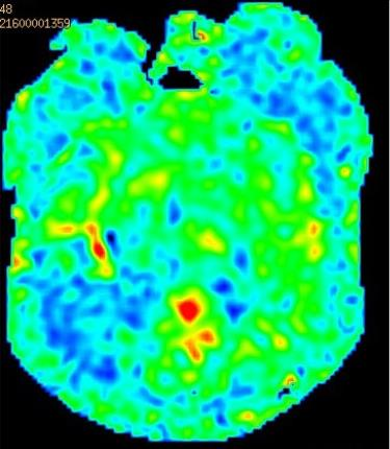

头颅核磁:颅内多发缺血灶;DWI未见明显高信号;灌注可见右侧半球低灌注

导丝怎么扩【载药时代 球扩天下】NOVA DES®颅内药物洗脱支架在颈内动脉颅内段重度狭窄中的应用体会二例!_https://www.jmylbn.com_新闻资讯_第19张

头颅MRA:右侧椎动脉闭塞可能,双侧颈内动脉末端、左侧椎动脉V4段重度狭窄可能。